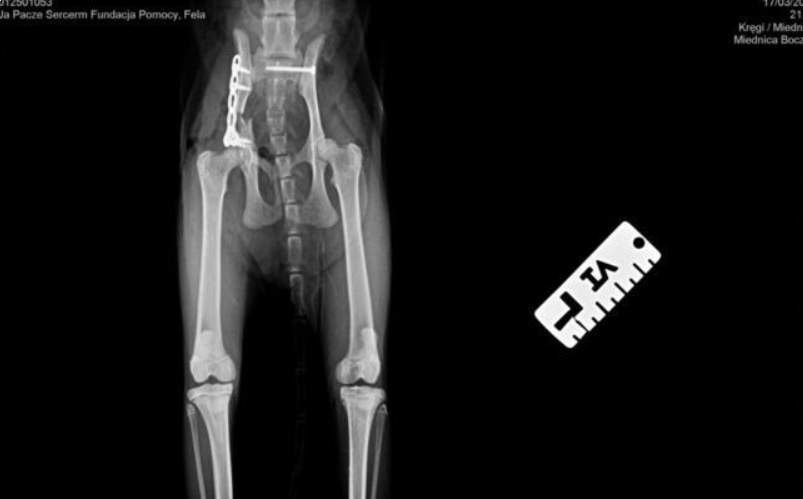

Kotka została znaleziona pod blokiem przez cudowną osobę, która nie pozostała obojętna i natychmiast powiadomiła odpowiednie służby! W wyniku upadku Felcia odniosła bardzo poważne obrażenia: przesunięcie kręgów w odcinku krzyżowym kręgosłupa, złamanie miednicy i zwichnięcie stawu biodrowego. Na szczęście zachowała czucie, więc mamy wielką nadzieję na powrót małej do pełnej sprawności, do czego długa droga...

Kicia jest już pod opieką naszej fundacji! Jest już po skomplikowanej operacji, której podjął się znakomity ortopeda, doktor Kacper Weigel. Z całego serca dziękujemy Panu doktorowi oraz całemu zespołowi Kliniki Weterynaryjnej Puławska za błyskawiczną pomoc i zaangażowanie! Wszystko się udało i po 6 tygodniowym unieruchomieniu w kennelu rozpoczniemy rehabilitację.